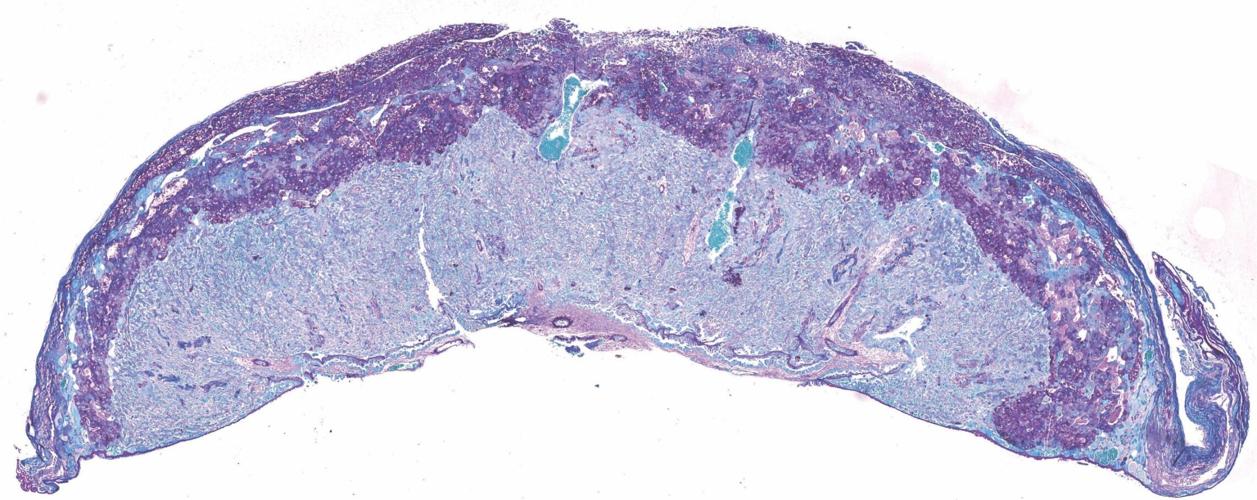

University of Cambridge scientists have discovered that the good gut bacteria Bifidobacterium breve in pregnant mothers regulates the placenta's production of hormones critical for a healthy pregnancy. (Jorge Lopez-Tello/ Cambridge University via SWNS)

Over 150 biological processes in the placenta - involving over 400 different proteins - were found to be different in mice with, and without, Bifidobacterium breve in their gut. (Jorge Lopez-Tello/ Cambridge University via SWNS)

kAmx? E96 DEF5J[ >@C6 E92? `d_ 3:@=@8:42= AC@46DD6D :? E96 A=246?E2 \ :?G@=G:?8 @G6C c__ 5:776C6?E AC@E6:?D \ H6C6 7@F?5 E@ 36 5:776C6?E :? >:46 H:E9[ 2?5 H:E9@FE[ q:7:5@324E6C:F> 3C6G6 :? E96:C 8FE]k^Am